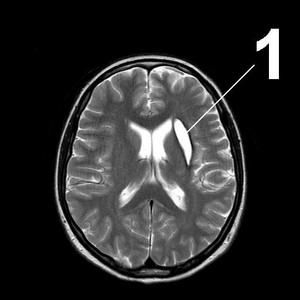

МР-томограммы мозга.1.     Киста после кровоизлияния в мозг2.    Кисты мозжечка после ишемического инсульта (закупорка мозговых артерий)3.     Кистозно-слипчивый арахноидит

Обследование и диагноз

МР-томография или КТ дадут однозначную информацию о наличии, размерах и расположении кисты. Отличить кисту от опухоли помогает исследование с внутривенным введением контраста: опухоль накапливает контраст, а киста – нет. Выполнить такое исследование Вы можете в Клинике Академии наук.

Чтобы избежать увеличения и появления новых кист, мы должны четко понимать и лечить первопричину их возникновения. Поэтому мы тщательно обследуем Вас на предмет нарушений кровообращения, инфекций, аутоиммунных заболеваний.